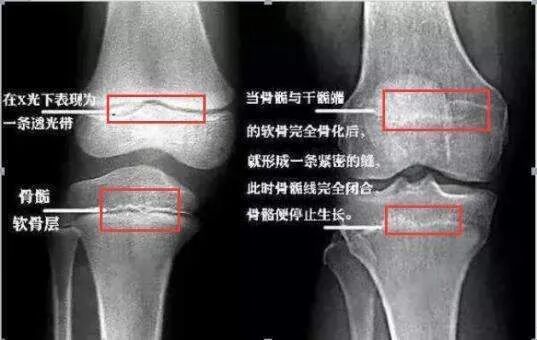

►骨龄:骨龄就是骨骼的年龄。它是以小儿骨骼实际发育程度与标准发育程度进行比较而得到的一个骨骼发育年龄。骨龄来判定人体成熟度比实际年龄更为确切,是国内外专家一致公认的、能精确反映骨骼生长状况和人体发育程度的重要指标。简单说法就是,身高不是由年龄决定的,而是由骨龄决定的。骨龄一旦闭合就没有办法再长高了!